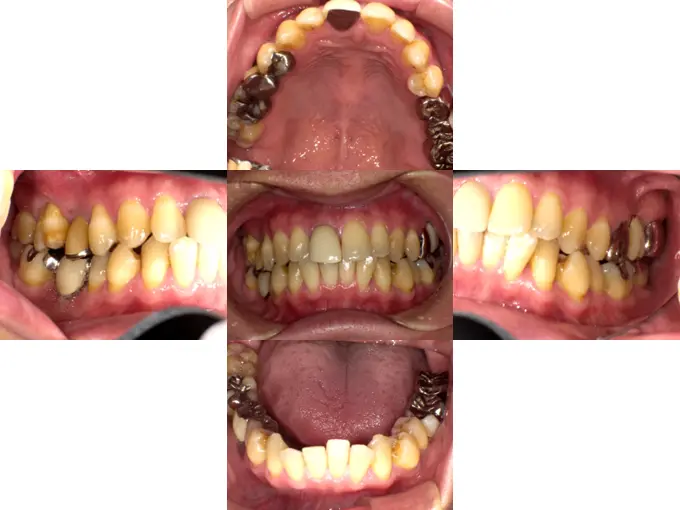

case13

症例13

-

歯の表面の赤と青の着色は咬み合せ確認の為の一時的なものです。

| 治療ケース | 骨造成(GBR)、インプラント埋入、オールセラミッククラウン |

| 治療結果 | 歯のない所を治療したいとの主訴で来院されました。虫歯や破折で抜歯が必要な状態でした。抜歯、骨造成(GBR)を行い待機期間を経て1次手術、2次手術を行いプロビジョナルを装着後問題の無いことを確認して最終上部構造を装着。歯が入った後経過も良く、安定している状態です。 |

| 治療開始月 | 2020年10月 |

| 治療期間 | 約7ヶ月 |